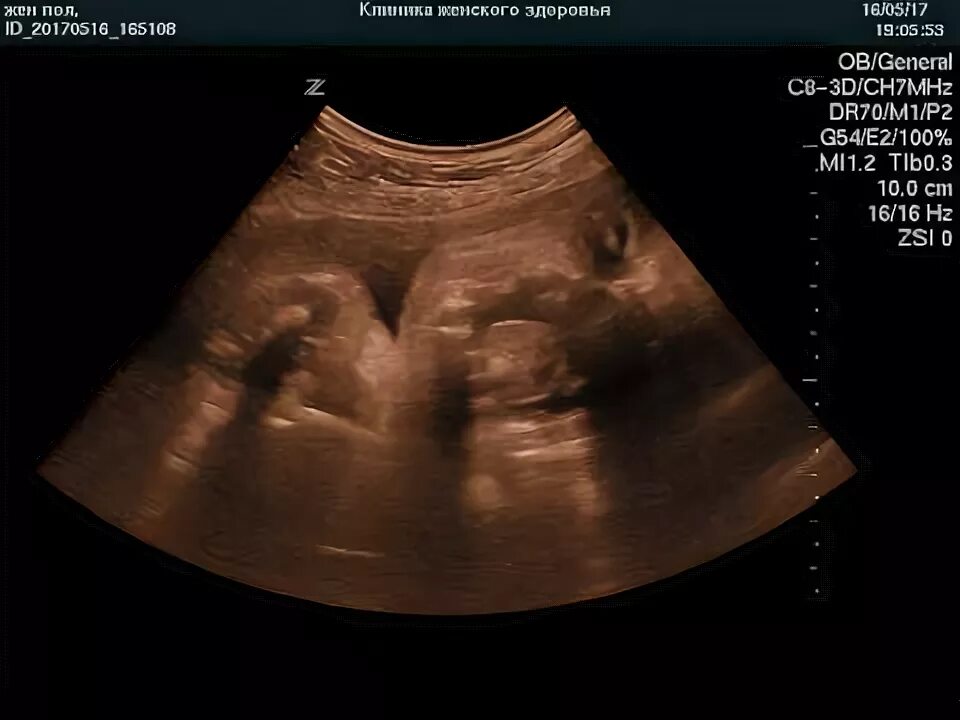

Через 20 недель